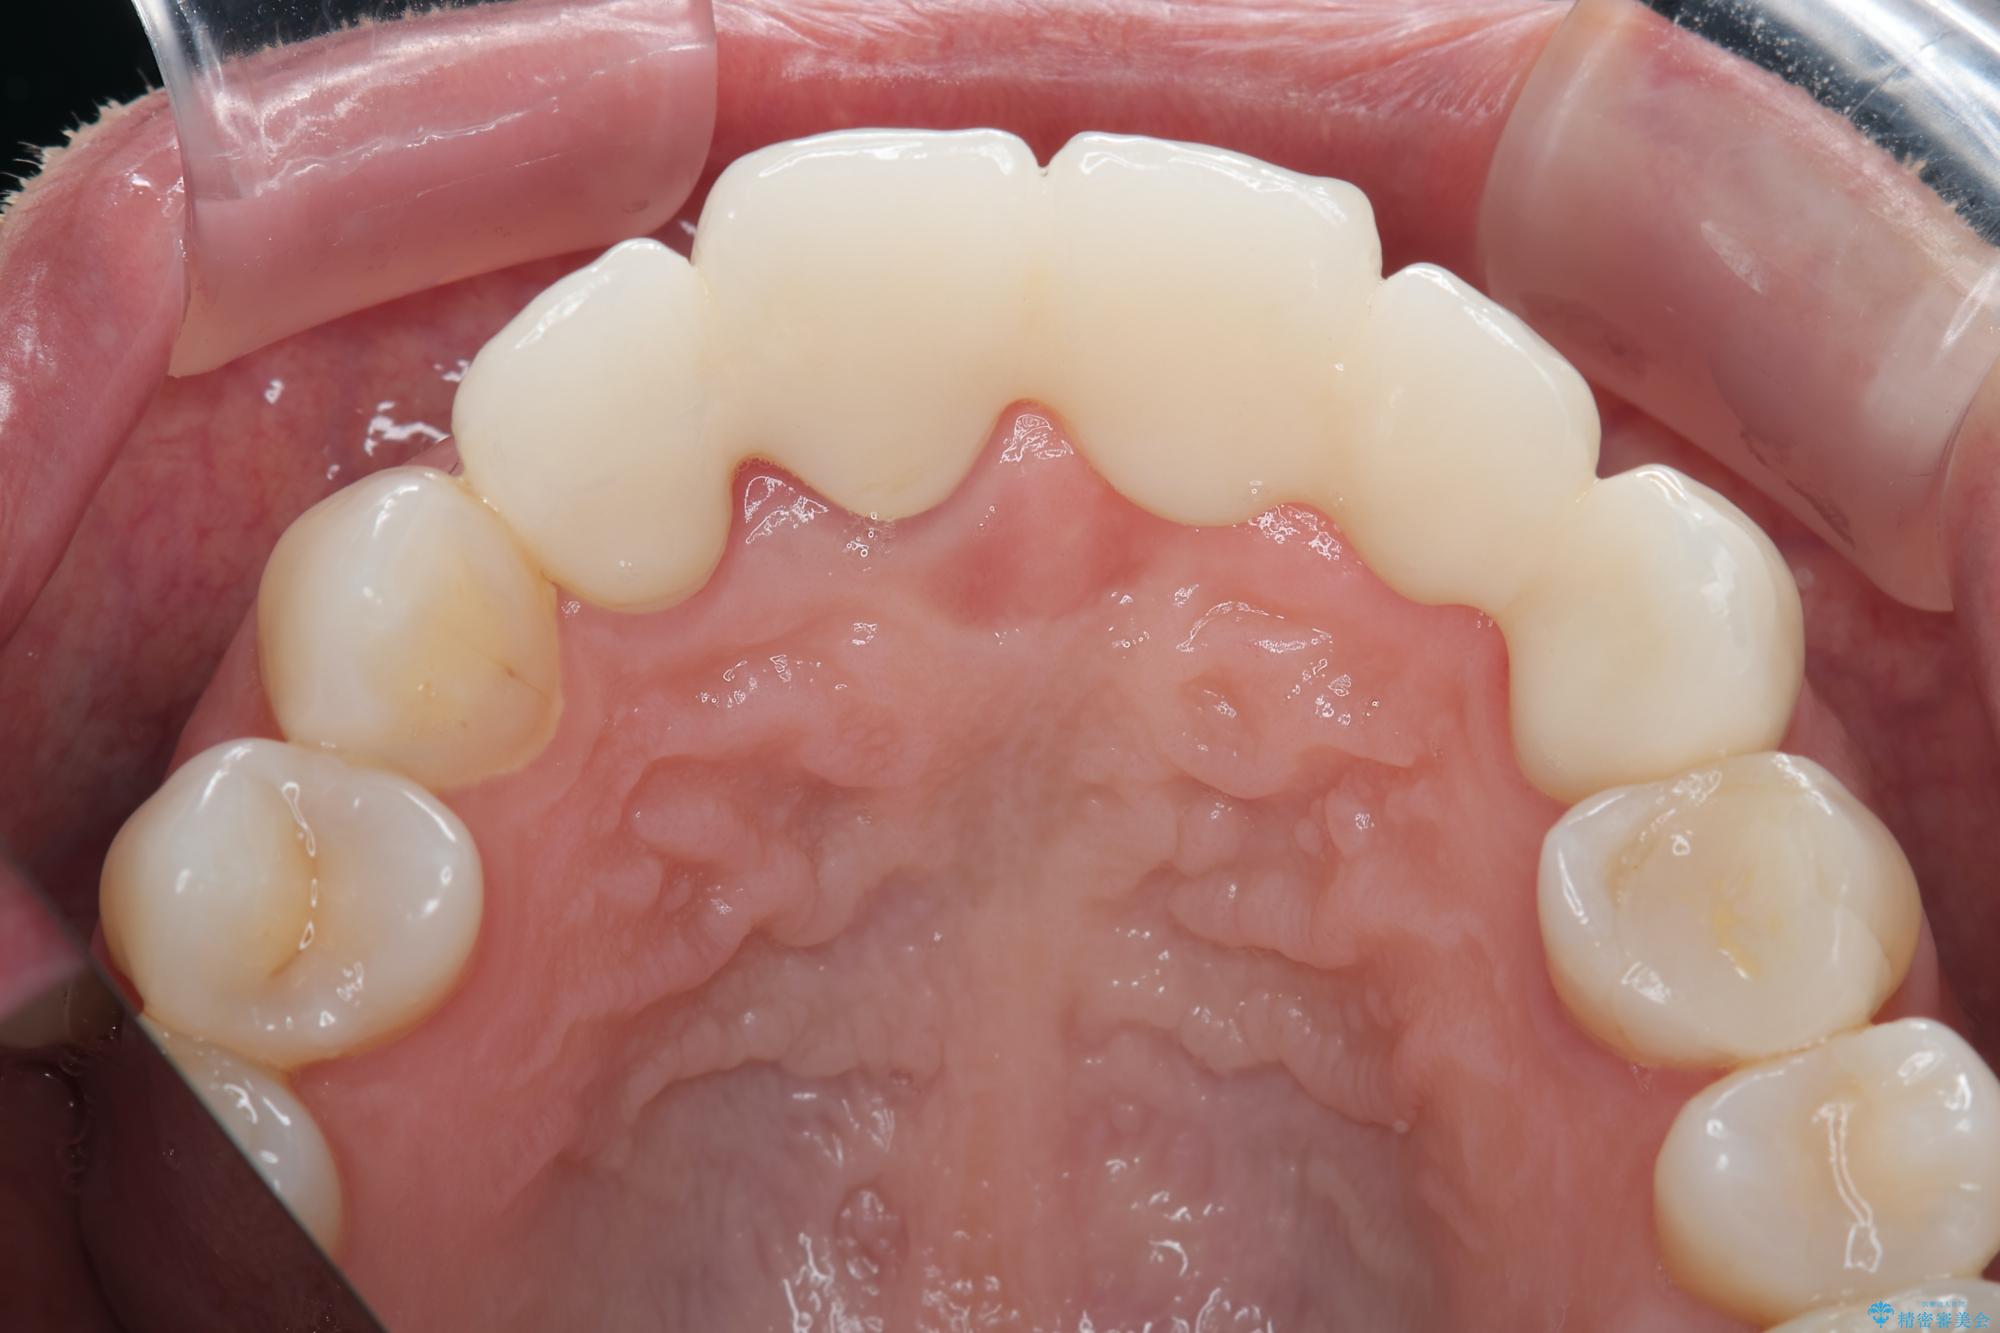

治療後

歯槽堤保存術を併用したブリッジ治療 治療後画像 歯槽堤保存術を併用したブリッジ治療 治療後画像 歯槽堤保存術を併用したブリッジ治療 治療後画像 歯槽堤保存術を併用したブリッジ治療 治療後画像 歯槽堤保存術を併用したブリッジ治療 治療後画像 歯槽堤保存術を併用したブリッジ治療 治療後画像 歯槽堤保存術を併用したブリッジ治療 治療後画像

抜歯時に可及的に歯肉のボリュームを保つよう骨充填材とコラーゲン製剤による填塞を行い審美的かつ機能的なブリッジとなるよう治療を進めます。